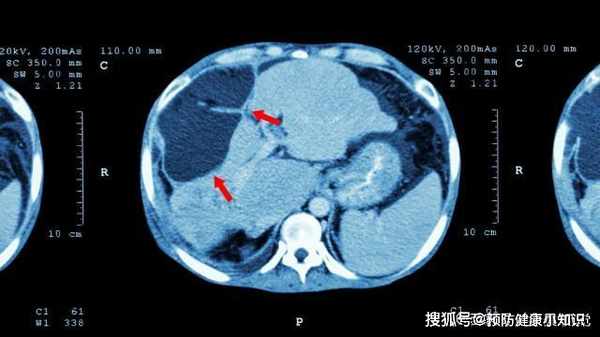

哪知,經過一系列詳細的檢查後,結果令他們吃驚:肝癌晚期,而醫生看了小王的臉色後,強烈建議讓小王也去檢查,結果顯示:也是肝癌晚期,父子倆再也忍不住了,蹲在醫院走廊裏抱頭痛哭,卻也無可奈何。

肝癌前期悄無聲息,為何一發現即到晚期?

中醫上講,肝是"啞巴器官",就算出現病變,也不會有疼痛的感覺,這就導致被很多人忽略,但真正有疼痛感時,往往已經是肝癌晚期,已經錯過最佳的治療時間。